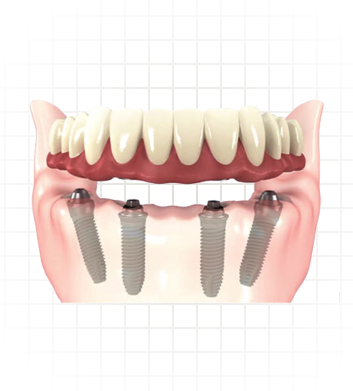

Hybrid Denture

Hybrid implant denture is a combination between both dental implants and traditional dentures. Hybrid denture is a full set of replacement teeth resting on dental implants (implant supported denture). With the arrival of the solid zirconia full-arch implant retained prosthesis we now have a prosthetic option that offers the stability and performance of dental implants with better cost.

Avoiding disadvantages of conventional dentures, hybrid dentures give better, non-fake appearance and are easier to maintain. Just like your natural teeth you need to brush them twice daily. Hybrid dentures are designed to be securely fit, fixed in place and permanent so they can only be removed by the dentist.